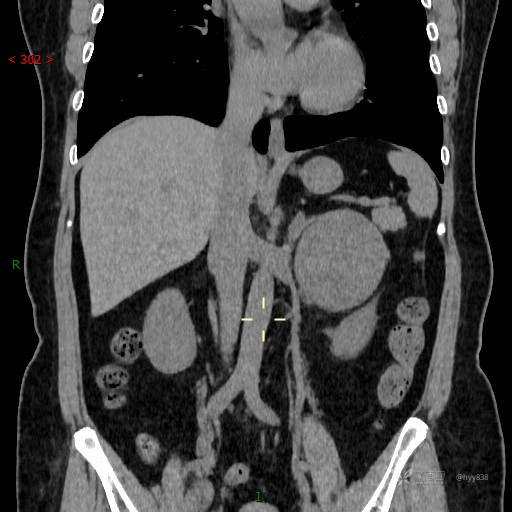

增强动脉期